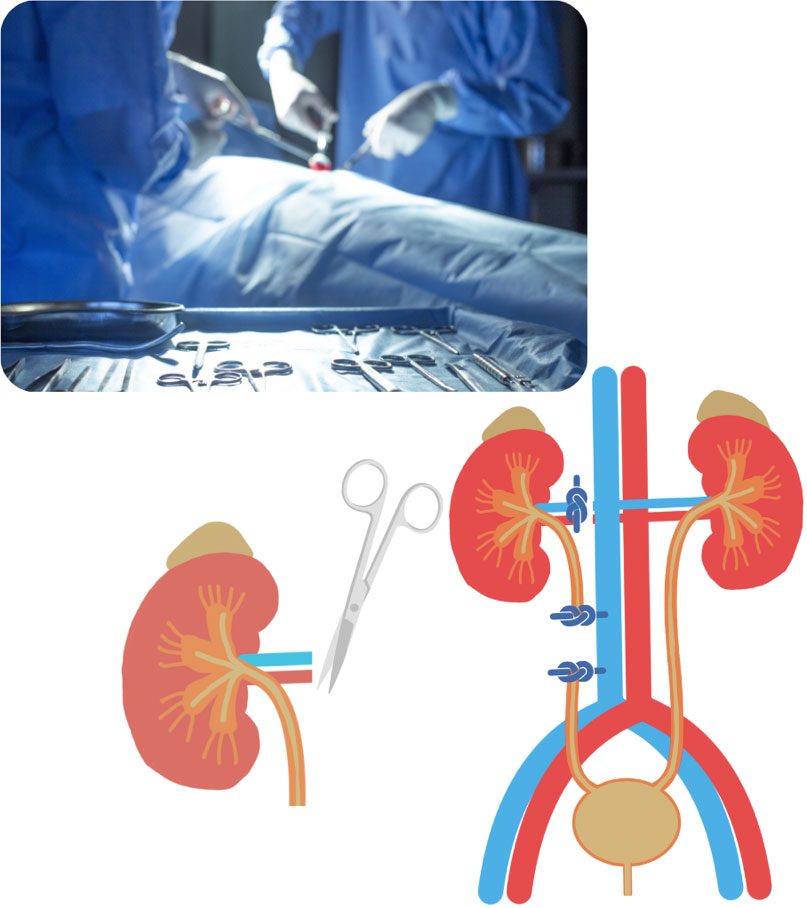

外科治療 閉塞を解除し、腎臓を守る重要な選択肢

1.尿管切開術(Ureterotomy)

手術の概要:

尿管を直接メスで切開し、結石を取り出す、最も直接的な手術方法です。

当院のこだわり:

猫の尿管は直径約0.4mmと非常に細いため、手術には高度な技術が求められます。当院では、手術用顕微鏡(マイクロサージェリー)を使用して、尿管のデリケートな組織を傷つけないよう、非常に精密な縫合を行います。

これにより、手術後の尿漏れや、尿管が狭くなってしまう(狭窄)といった合併症のリスクを最小限に抑え、尿の通り道を確保します。

2.尿管ステント留置術

尿管の中に、両端が「J」の字のようにカールした細いチューブ(ステント)を留置し、結石が残っていても尿が腎臓から膀胱へ流れるようにバイパスを作る手術です。

特徴

結石を完全に取り除くのが難しい場合や、尿管に損傷がある場合、または手術後に尿管が狭くなるのを予防するために選択されることがあります。

3.SUBシステム (Subcutaneous Ureteral Bypass)

近年、猫の尿管結石の治療において、特に従来の外科手術では対応が難しかった症例や、より長期的な尿流の確保が必要な症例で、このSUBシステム(皮下尿管バイパスシステム)が画期的な治療選択肢として注目されています。

これは、閉塞した尿管を迂回し、腎臓から膀胱へ直接尿を流す人工的な通路を体内に作成するものです。

SUBシステムってどんな仕組み?:

SUBシステムは、猫の尿管閉塞に対して開発された、腎臓と膀胱をつなぐ特別なチューブです。以下の3つの主要な部品で構成されています。

- 腎臓側カテーテル:

腎臓の中にある「腎盂(じんう)」という尿を集める部分に挿入され、腎臓で作られた尿を効率よく吸い出すチューブです。 - 胱側カテーテル:

膀胱の中に挿入され、腎臓側カテーテルから流れてくる尿を受け入れ、おしっことして体外へ排出する準備をします。 - 皮下ポート:

これら2つのカテーテルを体の皮膚の下(通常、肋骨の下あたり)でつなぐ「つなぎ目」のような装置です。このポートは、外から特殊な針を刺すことで、尿を採取したり、チューブが詰まりそうになったときに洗浄(フラッシング)したりするために使えます。これにより、体に負担をかけずにシステムのメンテナンスが可能です。

4.腎臓の摘出術 (Nephrectomy)

片方の腎臓が結石で完全に機能しなくなり、回復の見込みがない場合で、もう片方の腎臓が健康に機能している場合に、機能しない腎臓を摘出する手術です。

特徴:

両方の腎臓に問題がある場合や、残っている腎臓の機能が十分でない場合は、この手術は行われません。